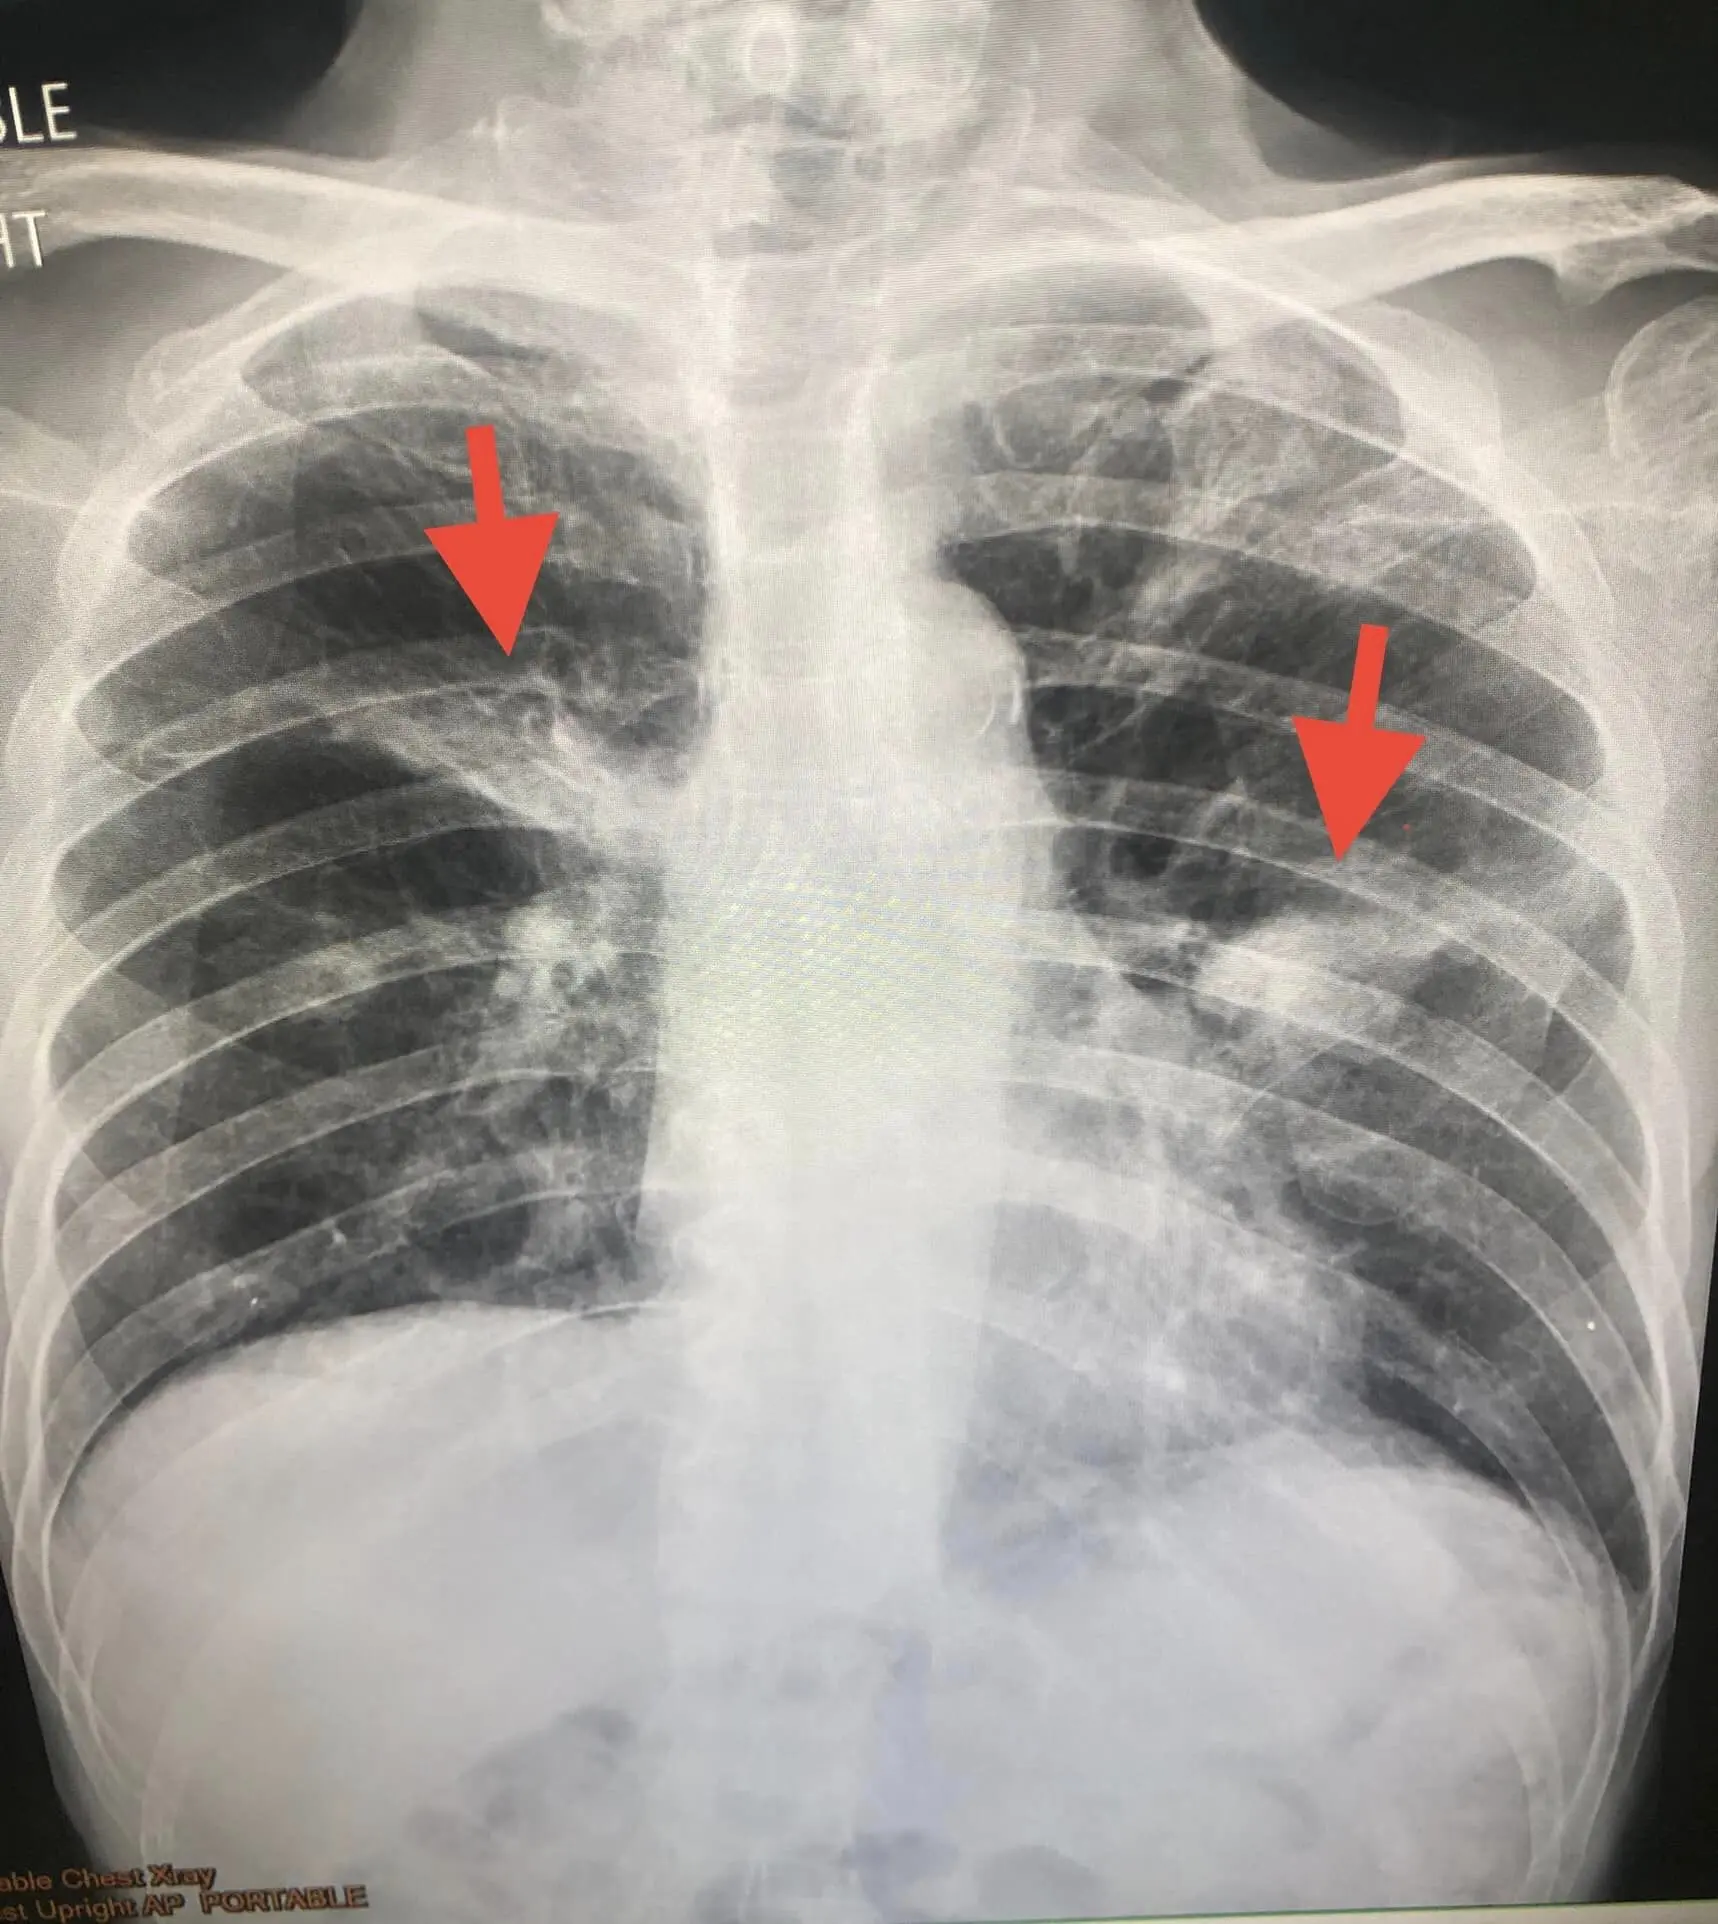

ล่าสุดเพจเฟซบุ๊ก หมอมนูญ ลีเชวงวงศ์ FC ได้ออกมาแชร์ภาพของปอดที่กำลังติดเชื้อ เป็นอีกหนึ่งภัยใกล้ตัว เวลารื้อหนังสือเก่า ๆ ในบ้านนำไปทิ้ง โดยระบุว่า ผู้ป่วยชายอายุ 79 ปีเตรียมย้ายบ้านที่บางแค กทม.ไปอยู่คอนโด ให้คนในบ้าน 2 คนรื้อหนังสือเก่า ๆ ที่เก็บสะสมไว้มากกว่า 20 ปี กระดาษหนังสือเปลี่ยนเป็นสีน้ำตาล เพื่อนำไปทิ้ง และเก็บไว้เพียงบางเล่ม ผู้ป่วยนั่งอยู่ในห้องหนังสือเป็นเวลา 2 ชั่วโมงขณะรื้อหนังสือ โดยไม่ได้ใส่หน้ากากอนามัย เมื่อวันที่ 16 กันยายน 2565 หลังจากนั้น 9 วันเริ่มมีไข้ ไอแห้งๆ เหนื่อยบ้าง

ผู้ป่วยเป็นโรคเส้นประสาทอักเสบแบบระยะเรื้อรัง (Chronic inflammatory demyelinating polyradiculoneuropathy หรือ CIDP หรือโรคซีไอดีพี) ทำให้แขนขาชาและอ่อนแรง 3 เดือน กำลังรักษาด้วยยาสเตียรอยด์ขนาดสูงและยากดภูมิเซลเซ็ป (cellcept) ตรวจร่างกาย มีไข้ อุณหภูมิ 38.1 องศาเซลเซียส ฟังเสียงปอดปกติ เอกซเรย์ปอดผิดปกติทั้ง 2 ข้าง

ทำคอมพิวเตอร์สแกนปอด พบโพรงเล็ก ๆ ในบริเวณปอดที่มีปื้นสีขาวหลายตำแหน่งในปอดทั้ง 2 ข้าง ส่องกล้องเข้าไปดูในปอด พบเสมหะสีขาวเล็กน้อย ส่งเสมหะที่ดูดจากหลอดลมไปตรวจ ย้อมพบเชื้อราสาย ไม่พบวัณโรค เพาะเชื้อราขึ้นแอสเปอร์จิลลัส ฟูมิกาทัส (aspergillus fumigatus) และ aspergillus spp อีกตัวหนึ่งไม่ทราบสปีชี่ส์ (ดูรูป) ส่งน้ำล้างปอดวัดระดับ bronchial aspergillus galactomannan ให้ผลบวก ยืนยันการติดเชื้อรา aspergillus

สรุปแล้ว ผู้ป่วยรายนี้มีภูมิคุ้มกันบกพร่องจากกินยาสเตียรอยด์และยากดภูมิ ติดเชื้อรา aspergillus จากการสูดดมหายใจสปอร์ของเชื้อรา aspergillus ที่เจริญงอกอยู่ในเนื้อกระดาษที่ชื้นของหนังสือเก่าๆลอยออกมาในอากาศขณะหนังสือถูกรื้อ เข้าไปในปอด ทำให้เกิดโรคแอสเปอร์จิลโลสิส ปอดติดเชื้อราแอสเปอร์จิลลัสชนิดรุกราน (invasive pulmonary aspergillosis)